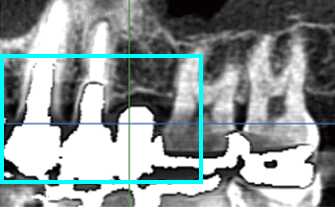

BioNaシミュレーション画像